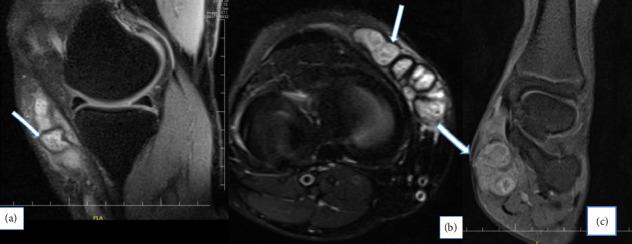

Mycetoma is a public health problem with a high prevalence in Africa. The study included 50 cases presenting at a tertiary care research hospital, retrospectively (cases we visited and followed up between November 2022 and March 2023) and prospectively between 1 August and 30 September 2024. Demographic characteristics, clinical features, physical examination findings, and diagnostic methods were reported. Out of 50 patients, 76% were male and 24% were female. The mean age (mean ± SD) of all cases was 35.50 ± 15.14. The most affected occupational group was farmers (44%). All patients presented with complaints of swelling. Symptoms continued for > 1-5 years in about 30 percent of cases. The diagnosis was made by pathological biopsy in 62% of the cases. The lower extremities were most commonly affected (80%), and subcutaneous soft tissue and muscle involvement was also commonly encountered. Bone involvement was higher in eumycetoma cases as compared to actinomycetoma. The frequency of myçetoma cases, which can involve all parts of the lower extremities, was determined, especially in Somali farmers. Difficulties in diagnosis and follow-up were analyzed.

足菌肿是一个在非洲高发的公共卫生问题。该研究纳入了一家三级医疗研究医院的50例病例,回顾性研究(2022年11月至2023年3月期间我们诊治和随访的病例)以及前瞻性研究(2024年8月1日至9月30日)。报告了人口统计学特征、临床特征、体格检查结果和诊断方法。50例患者中,76%为男性,24%为女性。所有病例的平均年龄(均值±标准差)为35.50±15.14。受影响最严重的职业群体是农民(44%)。所有患者均有肿胀主诉。约30%的病例症状持续超过1至5年。62%的病例通过病理活检确诊。下肢最常受累(80%),皮下软组织和肌肉受累也很常见。与放线菌性足菌肿相比,真菌性足菌肿病例的骨受累情况更严重。确定了足菌肿病例的发病频率,其可累及下肢的所有部位,尤其是索马里农民。分析了诊断和随访中的困难。